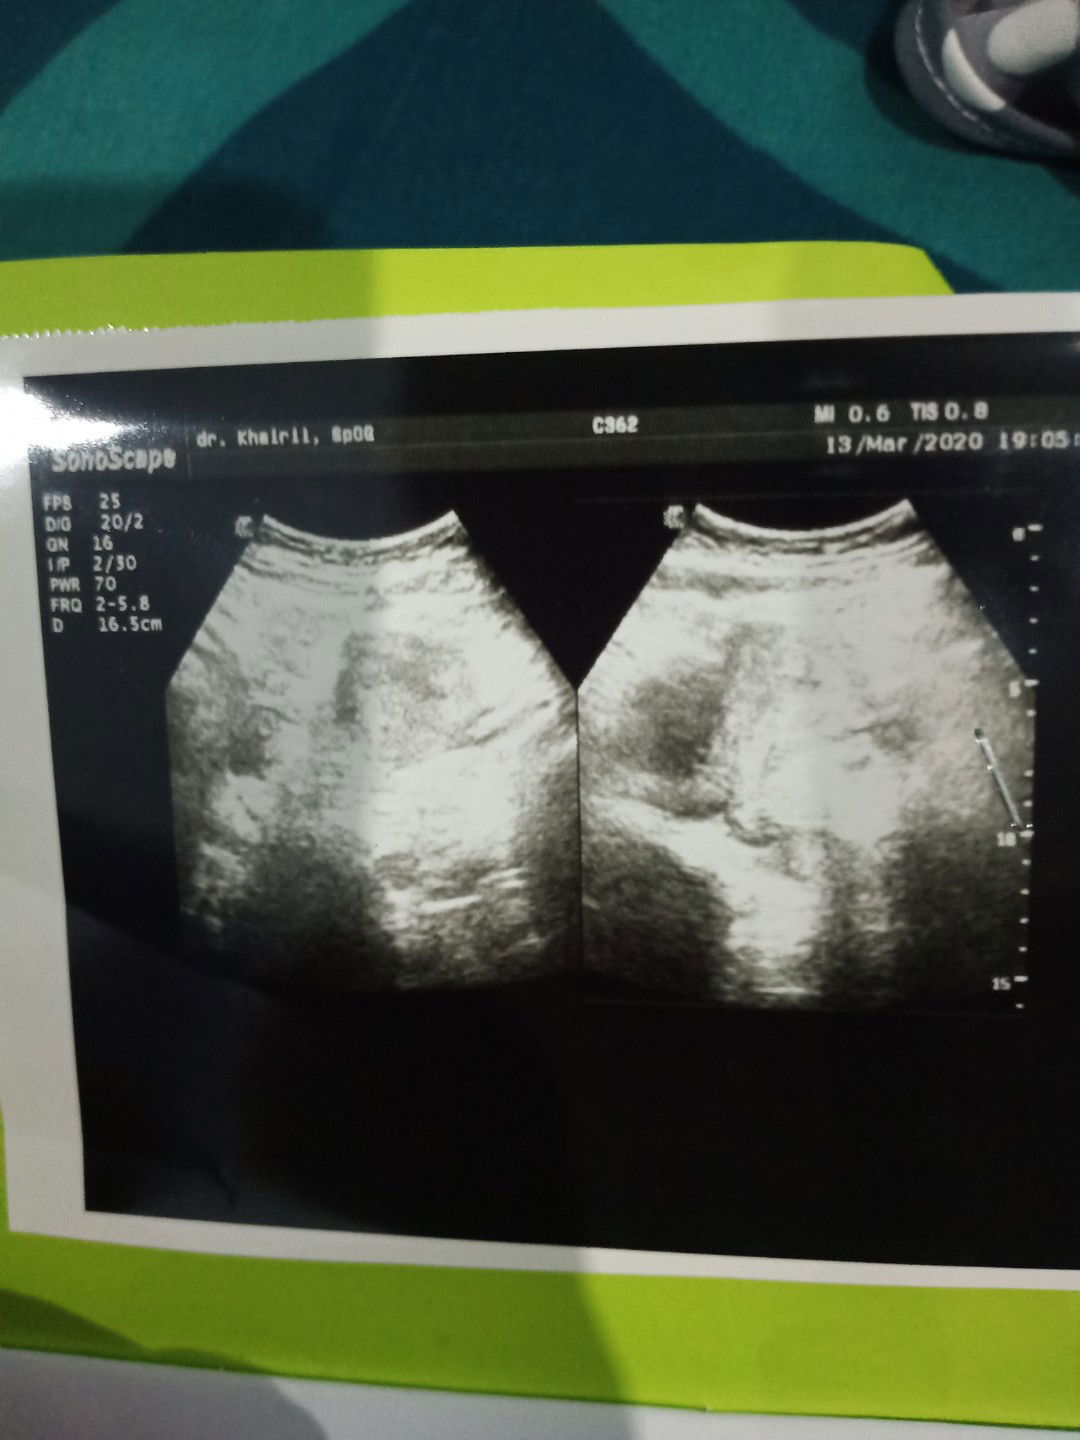

sudah berapa minggu kira" kehamilan sy??

Mohon penjelasanx

Pas 13 maret kemarin